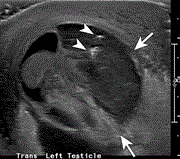

Scrotal abscess after a perforated appendicitis

Jonathan Keyes and others

Journal of Surgical Case Reports, Volume 2020, Issue 4, April 2020, rjaa058, https://doi.org/10.1093/jscr/rjaa058